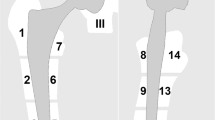

There are several basic methods to improve image quality and reduce metal artifacts when imaging metal implants. Basic sequence optimization steps include smaller nominal voxel size encoding (thinner slices, large image matrix), high receiver and RF pulse bandwidth, shorter echo times, and changing the direction of frequency and phase encoding directions. In addition, acquisition of fast spin-echo and STIR sequences rather than single spin-echo and gradient-echo sequences further reduces image artifact. However, changing the sequence parameters often leads to a reduction in SNR and the residual metal artifacts may be substantial, which is why advanced metal artifact reduction techniques such as view angle tilting (VAT), slice encoding for metal artifact correction (SEMAC), and multiacquisition variable-resonance image combination (MAVRIC) have been developed to further improve image quality (Figs. 4 and 5).

Advanced metal artifact reduction imaging of the hip after total joint arthroplasty in a 67-year-old patient (A–D). The implant is made of a titanium alloy. Adequate metal artifact suppression is demonstrated with a dedicated coronal slice encoding for metal artifact correction (SEMAC) turbo spin echo sequence, allowing diagnosis of the joint effusion surrounding the head of the femoral prosthesis (A, arrows). The SEMAC sequence shows the least artifacts compared to the axial short-tau inversion recovery (STIR) turbo spin echo sequence (B) with optimized inversion pulse (STIR WARP) and a high bandwidth (BW) T1-weighted turbo spin echo sequence (C) (bandwidth 425 Hz/pixel). The conventional radiograph (D) demonstrates normal fit of the prosthesis without signs of loosening. The images were acquired at 1.5 T with following sequence parameters: STIR SEMAC WARP—echo time (TE) 36 ms, repetition time (TR) 4220 ms, receiver bandwidth 500 Hz/pixel, inversion time (IT) 160 ms; transverse STIR WARP—TE 31 ms, TR 3830 ms, receiver bandwidth 450 Hz/pixel, IT 150 ms; T1 TSE High BW—TE 9 ms, TR 600 ms, receiver bandwidth 425 Hz/pixel

A 61-year-old patient with shoulder arthroplasty using implants made of titanium alloys. The radiograph (A) shows the large and complex implant with signs of loosening between the cement and the bone of the proximal humerus. The coronal short tau inversion recovery (STIR) turbo spin echo sequence (B) combined with compressed sensing (CS) and slice encoding for metal artifact correction (SEMAC) demonstrate only little artifacts within an acceptable acquisition time of 6:31 min and allows assessment of the fluid and increased signal around the implant indicating low-grade inflammation (outline arrows). After administration of intravenous contrast, the axial short-tau inversion recovery (STIR) turbo spin echo sequence (C) with optimized inversion pulse (STIR WARP) and a high bandwidth (BW) T1-weighted turbo spin echo sequence (D) (bandwidth 480 Hz/pixel) show a corresponding onion-like enhancement of the surrounding tissue (C, white arrows). Joint aspiration proved a low-grade infect with Cutibacterium acnes. The images were acquired at 1.5 T with following sequence parameters: STIR SEMAC—echo time (TE) 44 ms, repetition time (TR) 4500 ms, receiver bandwidth 780 Hz/pixel, inversion time (IT) 145 ms; STIR WARP—TE 33 ms, TR 4250 ms, receiver bandwidth 390 Hz/pixel, TI 160 ms; T1 TSE High BW—TE 10 ms, TR 648 ms, receiver bandwidth 480 Hz/pixels